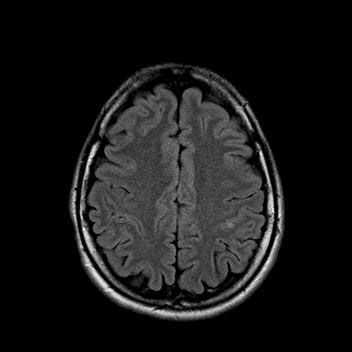

На МРТ головного мозга показаны лакунарные инфаркты в базальных ганглиях (вверху) и в белом веществе паренхимы головного мозга (внизу).

Компьютерная томография (КТ) головного мозга позволяет обнаружить большинство супратенториальных лакунарных инфарктов. Магнитно-резонансная томография (МРТ) головного мозга чётко выявляет как супра-, так и субтенториальные инфаркты (лакуны размером 7 мм и более), а также распространение в серое вещество кортикальной поверхности малого инфаркта в области белого вещества мозга. Такое распространение является преимущественно следствием эмболии, а не сужения просвета (окклюзии) мелких пенетрирующих сосудов. Поэтому в подобных ситуациях не следует ставить диагноз лакунарного инфаркта.